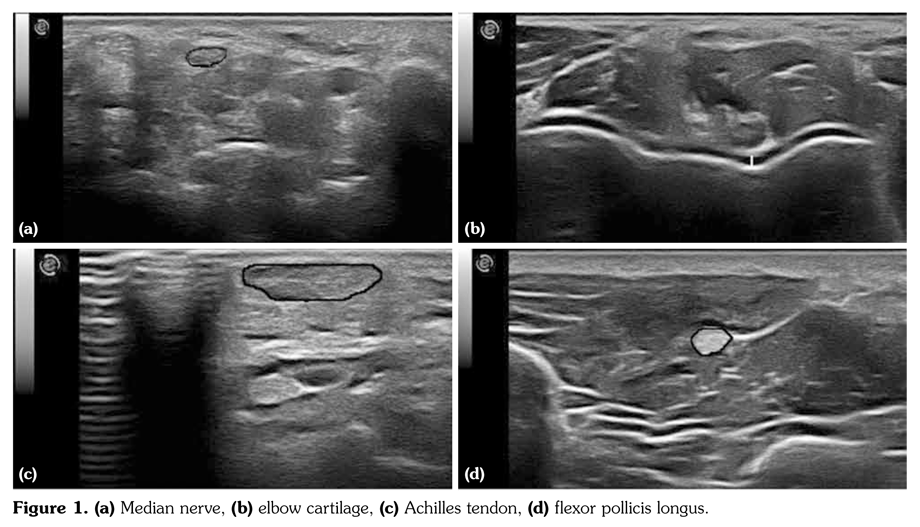

All subjects were examined with a commercial, real-time equipment (Esaote, Mylab 60, Genova, Italy) using a 6-18 MHz linear array transducer following a standardized scanning method. The same physician, experienced in musculoskeletal US, who was blinded to patients’ data performed all the ultrasonographic measurements involving distal humeral cartilage thickness, cross sectional area (CSA) for flexor pollicis longus (thenar region), Achilles tendon (at the level of the medial malleolus), and median nerve (at carpal tunnel entrance) (Figures 1a-d). To increase the accuracy of measurements, all images were also evaluated by another researcher experienced in US for more than 5 years.

Median nerve, flexor pollicis longus and Achilles tendon CSA, and humeral cartilage thickness values are summarized in Table 2. All parameters were significantly higher in acromegaly patients compared to control subjects (p<0.001). Median nerve measurements were similar between acromegaly subjects, with and without paresthesia symptoms (p>0.05). When active (n=22) and inactive (n=16) acromegaly patients were compared, only median nerve CSA values were greater in the former group bilaterally (p<0.05, Table 3). Although US measurements were correlated among each other, they did not show any significant correlation with GH/IGF-I levels or disease/ treatment duration (p>0.05).